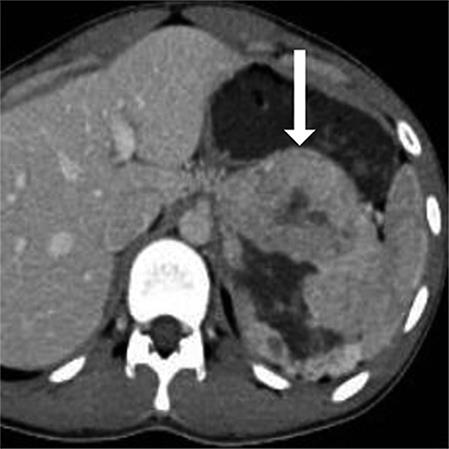

• 胃管引导下经肛减压管置入在直肠癌肠梗阻患者中的应用

2024, 49(2):183-187. DOI: 10.13406/j.cnki.cyxb.003421

摘要 (58) HTML (24) PDF 3.40 M (101) 评论 (0) 收藏

摘要:目的 探讨胃管引导下经肛减压管置入治疗直肠癌合并肠梗阻的可行性。方法 回顾分析2018年1月至2022年2月收治的55例直肠癌肠梗阻的患者资料,该55例患者采用胃管引导下经肛置入减压管,统计其成功率、肠梗阻的临床缓解率以及出血、穿孔等并发症的发生率,记录术后1年的随访情况。结果 55例患者有51例置管成功,技术成功率92.7%;临床完全缓解47例、临床部分缓解2例、临床无缓解2例,临床成功率96.1%;1例置管后3 d因不慎牵扯导致管道脱落,再重新成功置入;无出血、穿孔等并发症;1例置管失败和2例因置管后减压效果差患者行急诊开放手术;52例行择期手术,其中1例开放手术、51经腹腔镜辅助下手术;术后1年随访发现肝转移1例,其余54例无局部复发及远处转移,无死亡病例。结论 一次性胃管引导下可更加高效、安全地经肛置入减压管,有效地解除直肠癌导致的肠梗阻,适合在没有消化内镜设备的基层医疗单位推广使用。